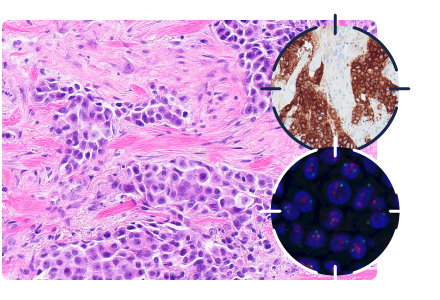

Ces biopsies ramènent de petits cylindres tissulaires sur lesquels le pathologiste peut poser un diagnostic précis. On peut ainsi éviter plusieurs chirurgies non nécessaires, avoir une idée précise des tumeurs malignes et choisir d’emblée le traitement approprié. Les divers marqueurs nécessaires au traitement personnalisé peuvent être évalués sur ces biopsies (récepteurs hormonaux – HER2 – Ki67 – PDL1).

Carcinome canalaire infiltrant bien différencié exprimant les récepteurs à l’œstrogène (récepteur hormonal).

Carcinome canalaire infiltrant pauvrement différencié avec surexpression de la protéine HER2 (immunohistochimie) et l’amplification du gène HER2 (FISH).